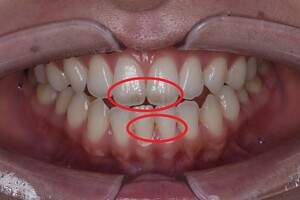

歯石除去

| 治療内容 | 初診検査・歯石除去 |

| 治療期間 | 2週間 |

| 費用 | 合計:約4,000~5,000円 内訳 初診料:約3,000~4,000円 (保険診療) 歯石除去:約1,000円 (2023年1月現在) |

| リスク・副作用 | ・歯肉の炎症がある場合は歯石除去中に出血を伴う可能性があります。 ・処置後に歯がしみることがあります。 ・歯茎の炎症が軽減すると歯茎が引き締まり、歯が長く見えることがあります。 |

| 治療方針 | 前歯部に叢生(歯列不正)があり多量の歯石が認められました。炎症の抑制を優先するため初診時はTBIのみ行い、2回目以降で歯石除去を行いました。今後は縁下歯石(歯ぐきの中に付着する歯石)の除去を全顎的に行っていく予定です。 |

| 担当者所見 | 叢生(そうせい)とは歯が折り重なるようにデコボコにはえている状態をいいます。歯ブラシが難しく磨き残しをしやすい為、普段使用している歯ブラシに加えワンタフトという細かい部分も磨くことのできる小さな毛束の歯ブラシの使用をおすすめしました。 |

| 担当者所見 | 歯石の存在は感じていたものの歯科医院に苦手意識が強く3年ほど放置していたとのことでした。 舌で触った時にザラザラすることや口臭も気になった為、今回意を決してご来院くださいました。 ブラッシング指導を熱心に聞いてくださり、セルフケアで歯肉の炎症を抑えた上で歯石除去ができたのでお痛みが少なく行えました。 患者様も苦手意識が克服できたと喜んでくださり、今後の治療にも積極的な姿勢です。 |